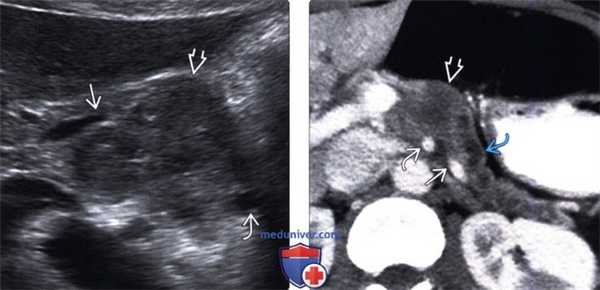

(Левый) На поперечном УЗ срезе брюшной полости визуализируется крупное гипоэхогенное объемное образование тела поджелудочной железы, сужение селезеночной вены вблизи слияния ее с воротной веной. Дистальная часть тела поджелудочной железы скрыта; однако панкреатический проток выглядит расширенным.

(Правый) При КТ с контрастным усилением также выявляется инфильтративное образование тела поджелудочной железы, окружающее селезеночную вену до места ее впадения в воротную вену и соприкасающееся с верхней брыжеечной артерией. Обратите внимание на расширение панкреатического протока и атрофию паренхимы поджелудочной железы выше уровня опухоли.